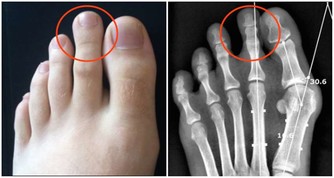

①做好保暖工作,春天最好不要剪短髮甚至剃光頭, 晨起最好不要馬上洗頭,洗完頭就要用吹風頭吹乾,外出要戴帽子,在早春,一定要穿純棉背心或針織純棉馬甲,注意腹部及背部保暖。若經常覺得腹部涼, 午睡時可以雙手搓熱後進行摩腹,一分鐘30~50次每次約5分鐘; 經常覺得背部涼颼颼的老年人,可以用炒熱的薑片(炒熱5秒鐘)搓一搓後背部, 以祛風寒之邪在家裡不要光著腳,一定要穿純棉襪或者毛拖鞋。